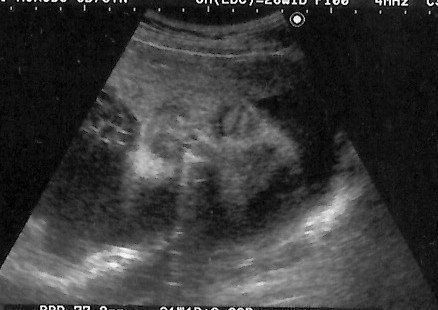

チャーミー小結さんの妊娠28週目のエコー写真

指を開いて見せているところ?この頃から「ぽん太」はおなかの中でよく伸びをしていて、胃が押し上げられました。入院してからは毎日誰かの赤ちゃんが誕生し、新生児室のガラス越しに並んだベビーたちを眺める楽しみも加わりました。